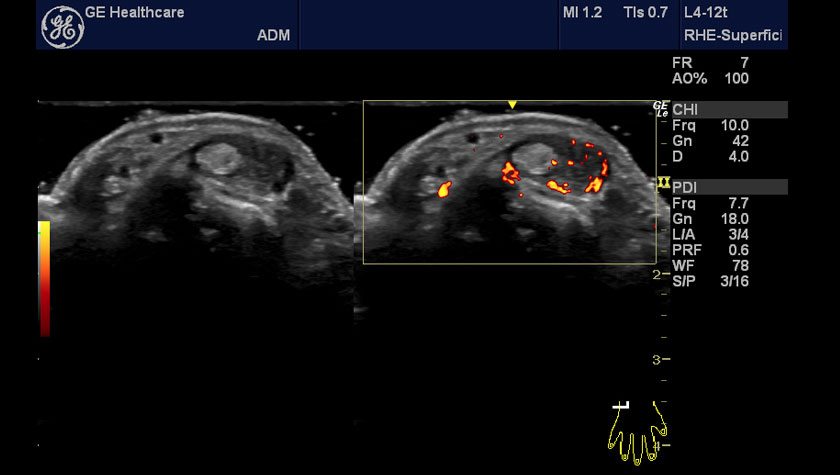

Галерея изображений:

1 - ревматология, кисть, датчик L4-12t-RS